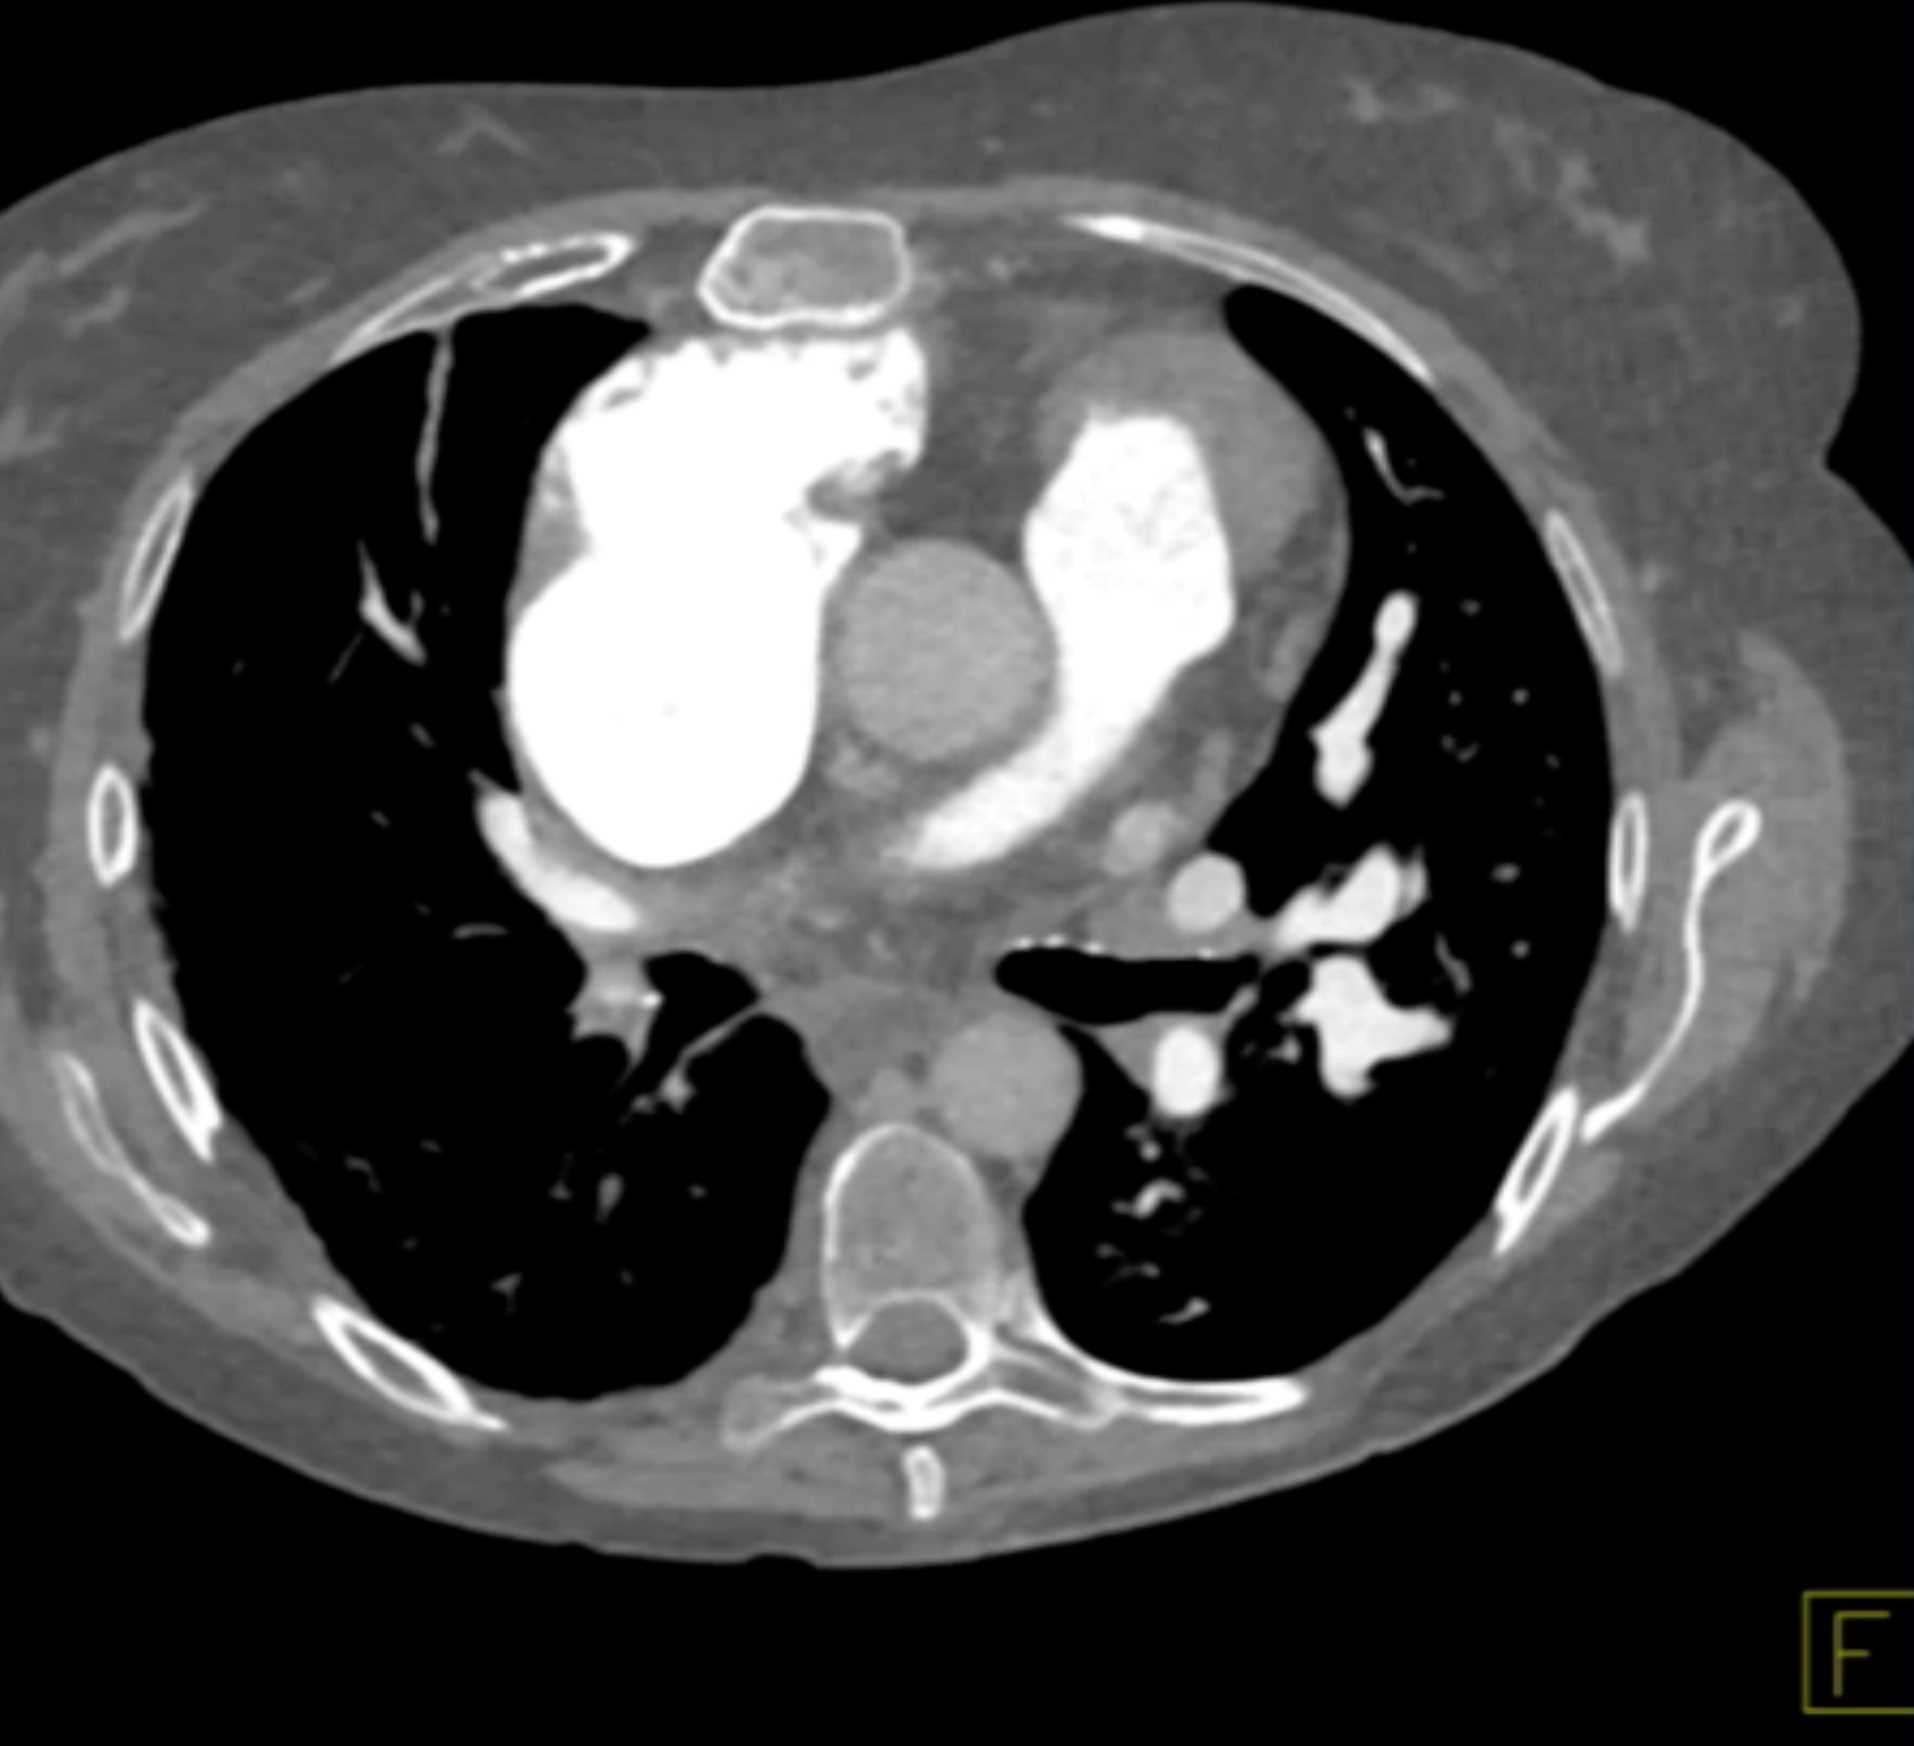

Fibrosing Mediastinitis involves the Pulmonary Artery and Vein